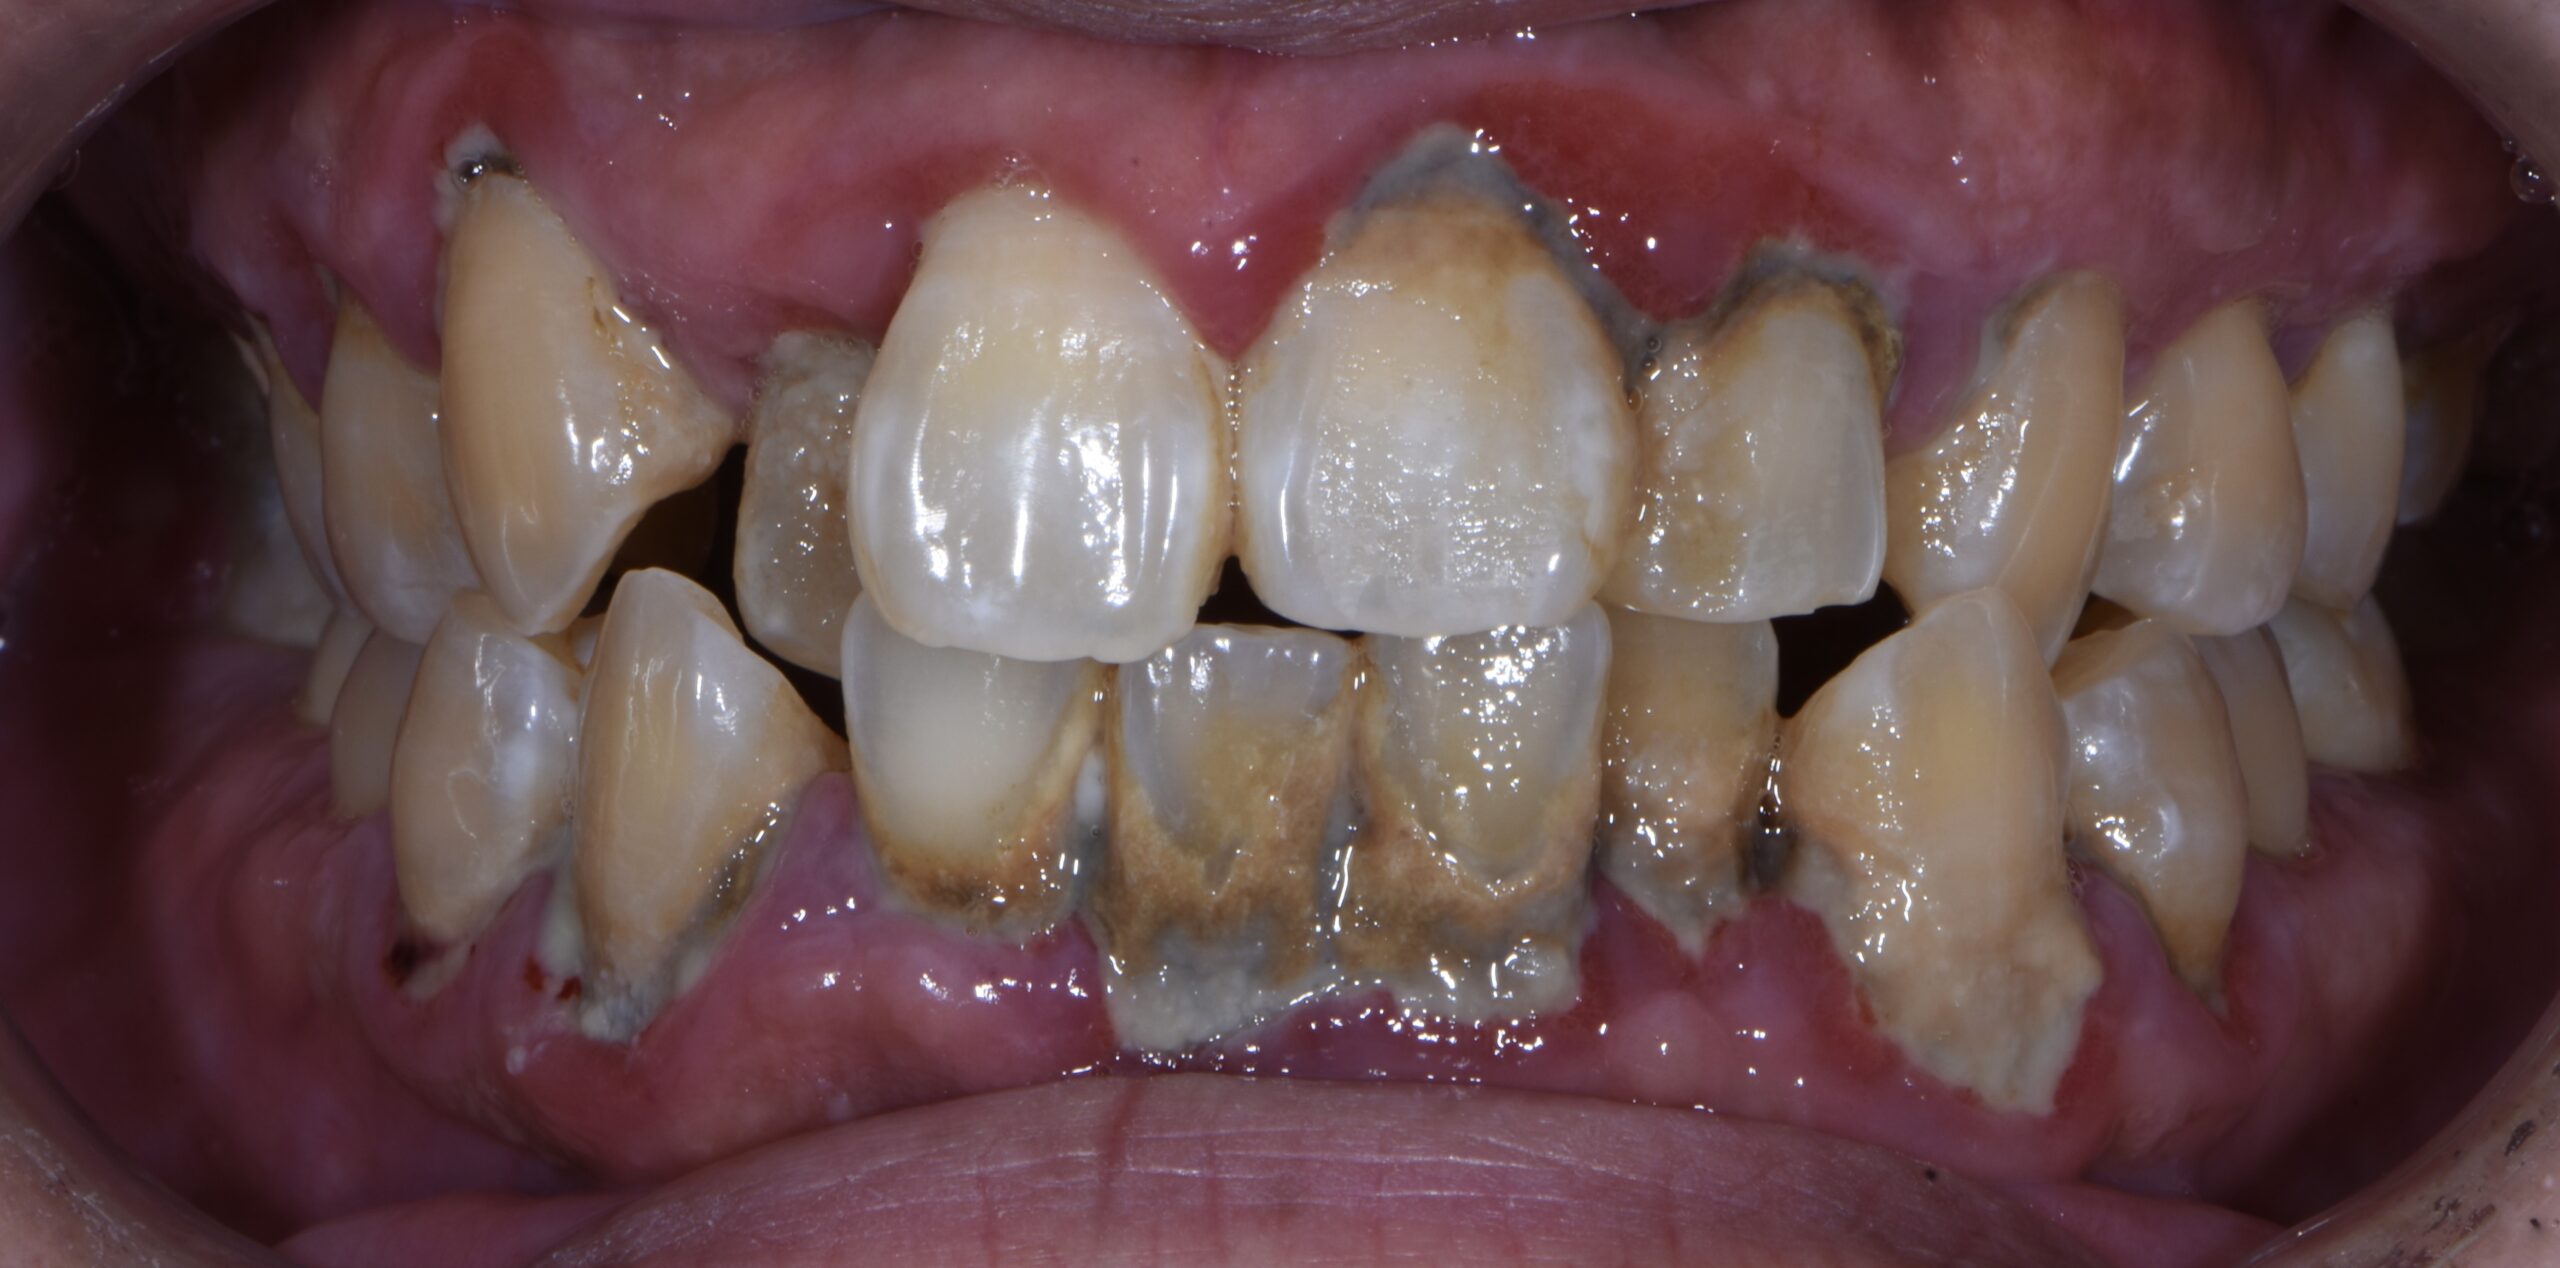

歯石除去を中心とした予防歯科治療

- 主訴

- 歯ぐきから出血する。口臭が気になる。

- 治療内容

- 歯科衛生士による歯磨き指導と超音波スケーラーによる歯石除去を行いました。

- 治療期間

- 3ヶ月

- 治療費用

- 健康保険適用

- 治療のリスク

- 一過性に知覚過敏になる事があります。

BEFORE

AFTER